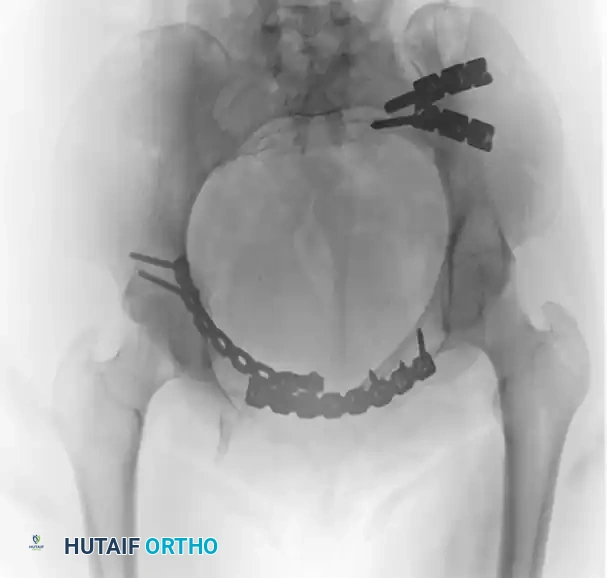

FIGURE 56-47 & 56-48: Denis classification of sacral fractures, differentiating three zones of injury: Zone I (sacral ala), Zone II (foraminal region), and Zone III (spinal canal). The most medial fracture extension classifies the injury. Accompanied by 40-degree caudal inlet and 40-degree cephalad outlet views of the pelvis.